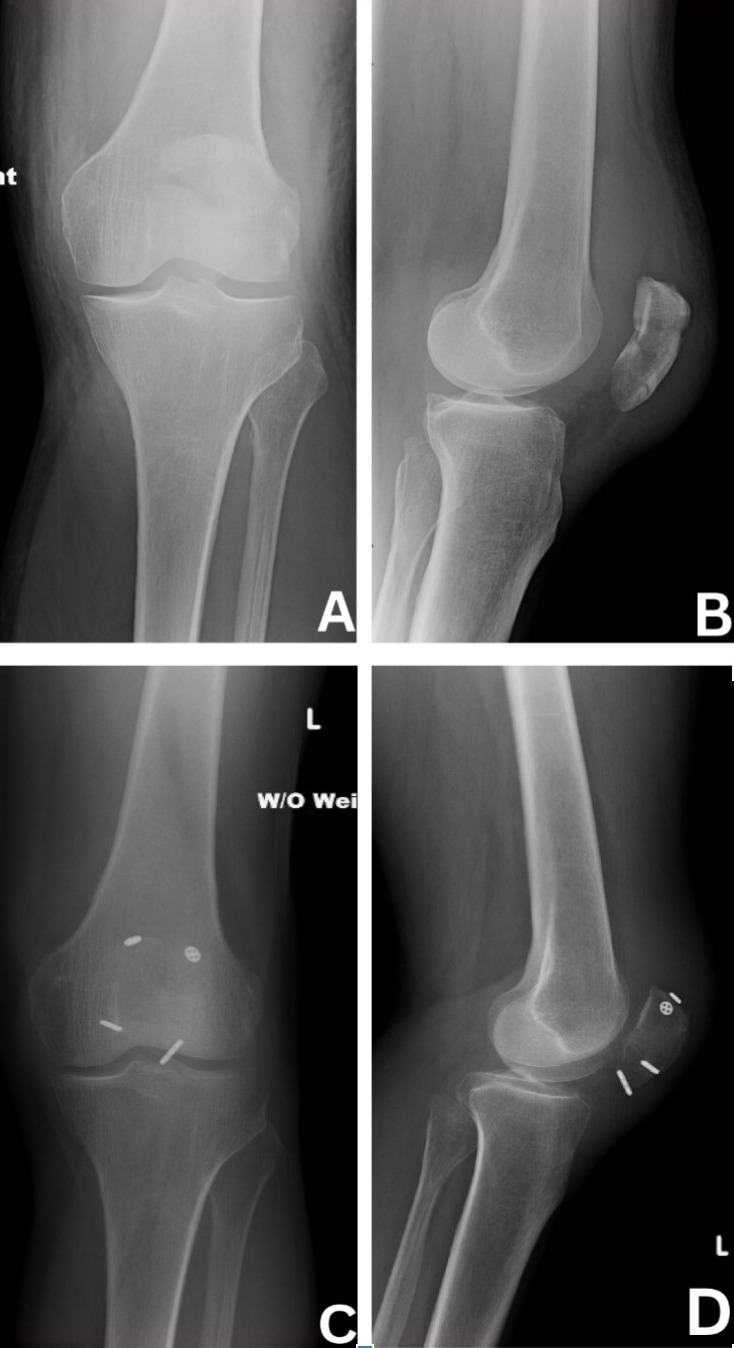

All patients were placed in the supine position with a tourniquet on the upper thigh, which was inflated prior to incision. An incision was made centered over the patella and dissection was carried down to the fracture site with care to avoid damage to the quadriceps and patellar tendons. After irrigation of the fragments, fluoroscopy was utilized to ensure proper reduction with clamps. Medial and lateral K-wires were then driven across the fracture in a perpendicular fashion (Figure 1). Proper placement was ensured via fluoroscopy. A small incision was then made through the quadriceps tendon to create room for a 3.5 mm cannulated overdrill along the K-wire. This step was repeated on the patellar tendon site. This allowed passage of our suture buttons (Arthrex TightRopeTM) through each drill hole with a suture passer. At this point, buttons were then present in all four quadrants of the patella (Figure 2). Minimal tensioning of the suture buttons was then performed.

A braided polyester and ultra-high molecular weight polyethylene suture (Arthrex FiberWire or SutureTapeTM) was then placed over the suture button ends in a figure-of-eight manner (Figure 3). Suture buttons were each sequentially tensioned with the knee in full extension, which secured the FiberWire/Suture Tape to bone. Finally the figure-of-eight suture would be tied to complete the anterior tension-band.

Fluoroscopy was used to confirm appropriate reduction of the articular surface (Figure 5). The knee was then taken through range of motion to ensure there was no gapping while taking care not to compromise the repair. The wound was copiously irrigated and closed with close inspection of the retinaculum. If the retinaculum was disrupted, it was then repaired with a combination of SutureTape and Vicryl suture.